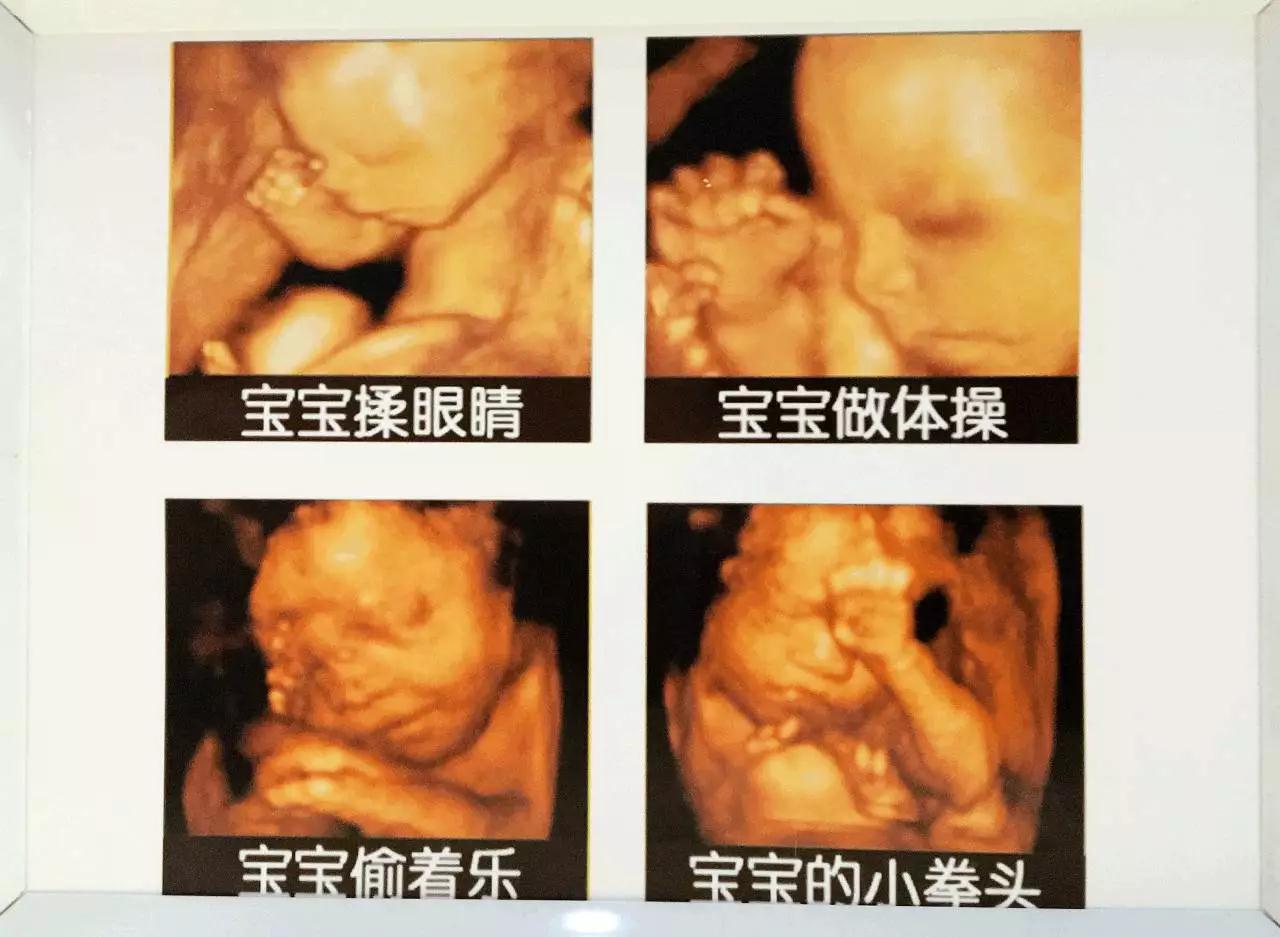

胎宝宝在妈妈肚子里

经过了段非常奇妙的旅程

胎宝宝在妈妈肚子里的日常